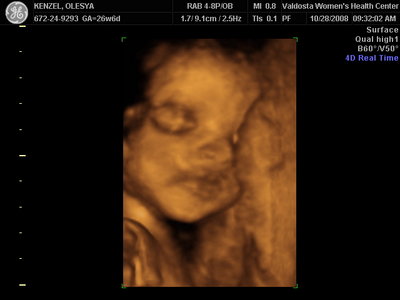

Еще одна Джианнка:

Вложения: |

KENZEL,OLESYA_5.JPG [ 60.02 КБ | Просмотров: 1229 ]

Катюш, какой прикольный бутузик ! Олесь, после фотки средней - точно прям похожи!

Ой, Ксюнь, класс!!! Я говорю у вас у всех очертания носика, губок видны отлично...у моей же все размыто как-то и везде разное. На одной фотке вообще не нос а аэродром. Я ничего не поняла. Но УЗИстка сказала что она очень близко к плаценте мордашкой была поэтому так мутно все. Я надеюсь они мне переделают бесплатно все же. Я бы очень хотела. Так рассмотреть охото как следует, за это ведь и платила как никак..:-)

Олеся ну красотка у тебя!! слушай еще один губастик будет  по моему ты зря, очен прилично лицо видно девочки у всех такие сладкие они на этих фотках